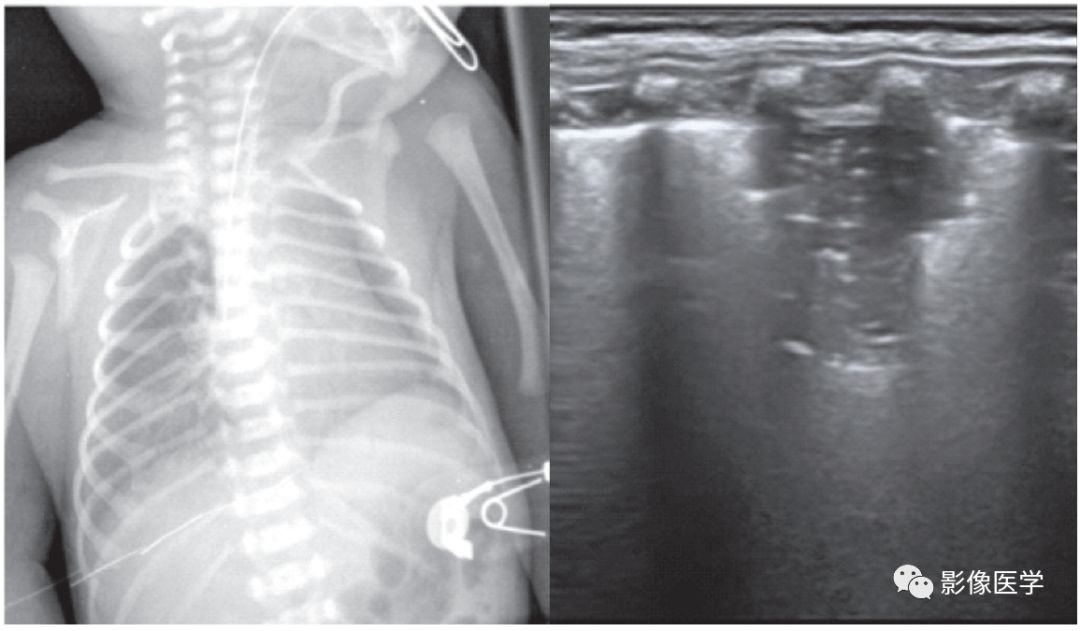

图 6-2 重症感染性肺炎(1)

胎龄38+2周,剖宫产分娩,出生体重3 420g。因呼吸困难3d于出生后20d入院。体温38℃,双肺可闻及密集细湿啰音。血常规:WBC 22×109/L,N 78%,单核细胞比例12.2%,CRP 66.8mg/L。胸部X线检查结果符合新生儿肺炎改变。肺脏超声显示双肺边缘不规则的大面积实变区伴支气管充气征,胸膜线模糊或消失,A线消失。